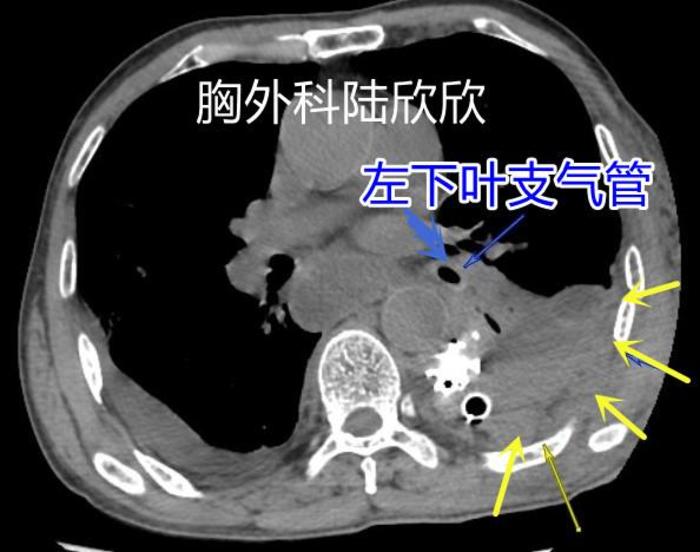

术后患者心脏不太好,但是咳嗽咳痰较好。但是几天以后,患者错误的认为自己每天只有两口痰,每天早上患者雾化吸入以后,咳出两口淡黄色粘痰以后,就认为一天的任务结束了,就不咳嗽了。我和病人的妻子来回劝,病人根本听不进去。又过来几天病人出现胸闷,再出现低烧,不超过37.5度。急诊CT检查发现患者有左下肺不张,左下肺被痰液堵塞后塌陷了

上图为图6。为术后第九天的CT。可见两个蓝色箭头指示的是左下叶支气管,再往下支气管就被堵死了。黄色箭头指示的是肺不张

上图为图7。左图是为术后第九天的CT。可见两个蓝色箭头指示的是左下叶支气管,远端肺不张。右图是为术后第十四天的CT。可见两个蓝色箭头指示的是左下叶支气管,远端肺重新复张